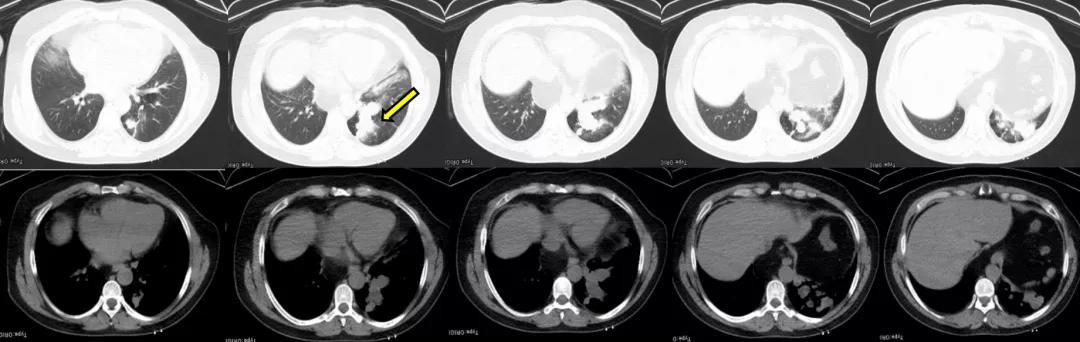

2019年12月5日胸部CT:1、左肺下叶后基底段见不规则团片影,较大层面约5.8×4.6cm,其内见少许点状钙化灶,周围见斑片、条索影,邻近胸膜增厚、黏连。2、右肺中叶、左肺下叶、左侧斜裂小结节,较大者约0.4cm,多系炎性。3、双肺少许慢性炎症。4、心脏未见增大,肺动脉干稍增粗。5、左肺门淋巴结稍大。6、食管裂孔疝。(图1)。

图1:胸部CT 2019年12月5日

2020年3月17日胸部CT:1、左肺下叶后基底段见不规则团片影,较大层面约6.2×5.1cm,其内见少许点状钙化灶,周围见斑片、条索影,邻近胸膜增厚、黏连。2、右肺中叶、左肺下叶、左侧斜裂小结节,较大者约0.4cm,多系炎性。3、双肺少许慢性炎症。4、心脏未见增大,肺动脉干稍增粗。5、左肺门淋巴结稍大。6、食管裂孔疝(图3)。

图3:胸部CT 2020年3月17日